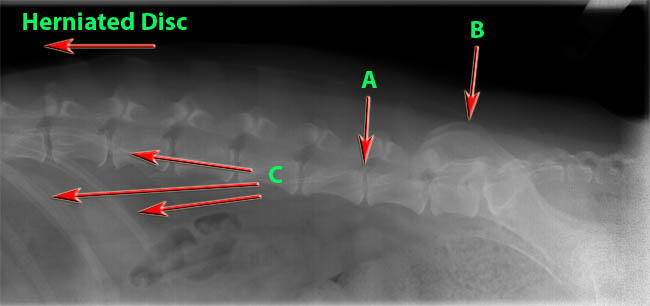

Exhibit 1:

Exhibit 1 A –

During the break-down stage  of disc, a calcium build up occurs which causes various issues. In this image the calcium build up is pushing up against the spinal cord causing brainwaves not to make it to other parts of the body. From disc A to the right is where the dysfunction is occurring. The calcium buildup is shown by where the end of the red arrow is pointing.

Exhibit 1 B –

The disc shown here is a healthy disc. You can see that there is no distortion in the x-ray. This is shown by the ‘black’ around where the red arrow is pointing.

Exhibit 1 C –

Both C red arrows are pointing to the ribs.